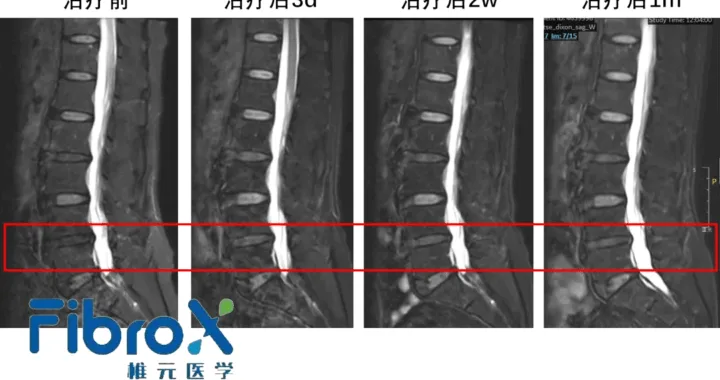

FibroX Therapeutics Secures IND Approval for FibroCell in Lumbar Disc Degeneration

Shanghai‑based FibroX Therapeutics announced that its investigational new drug (IND) application for FibroCell, an allogeneic...